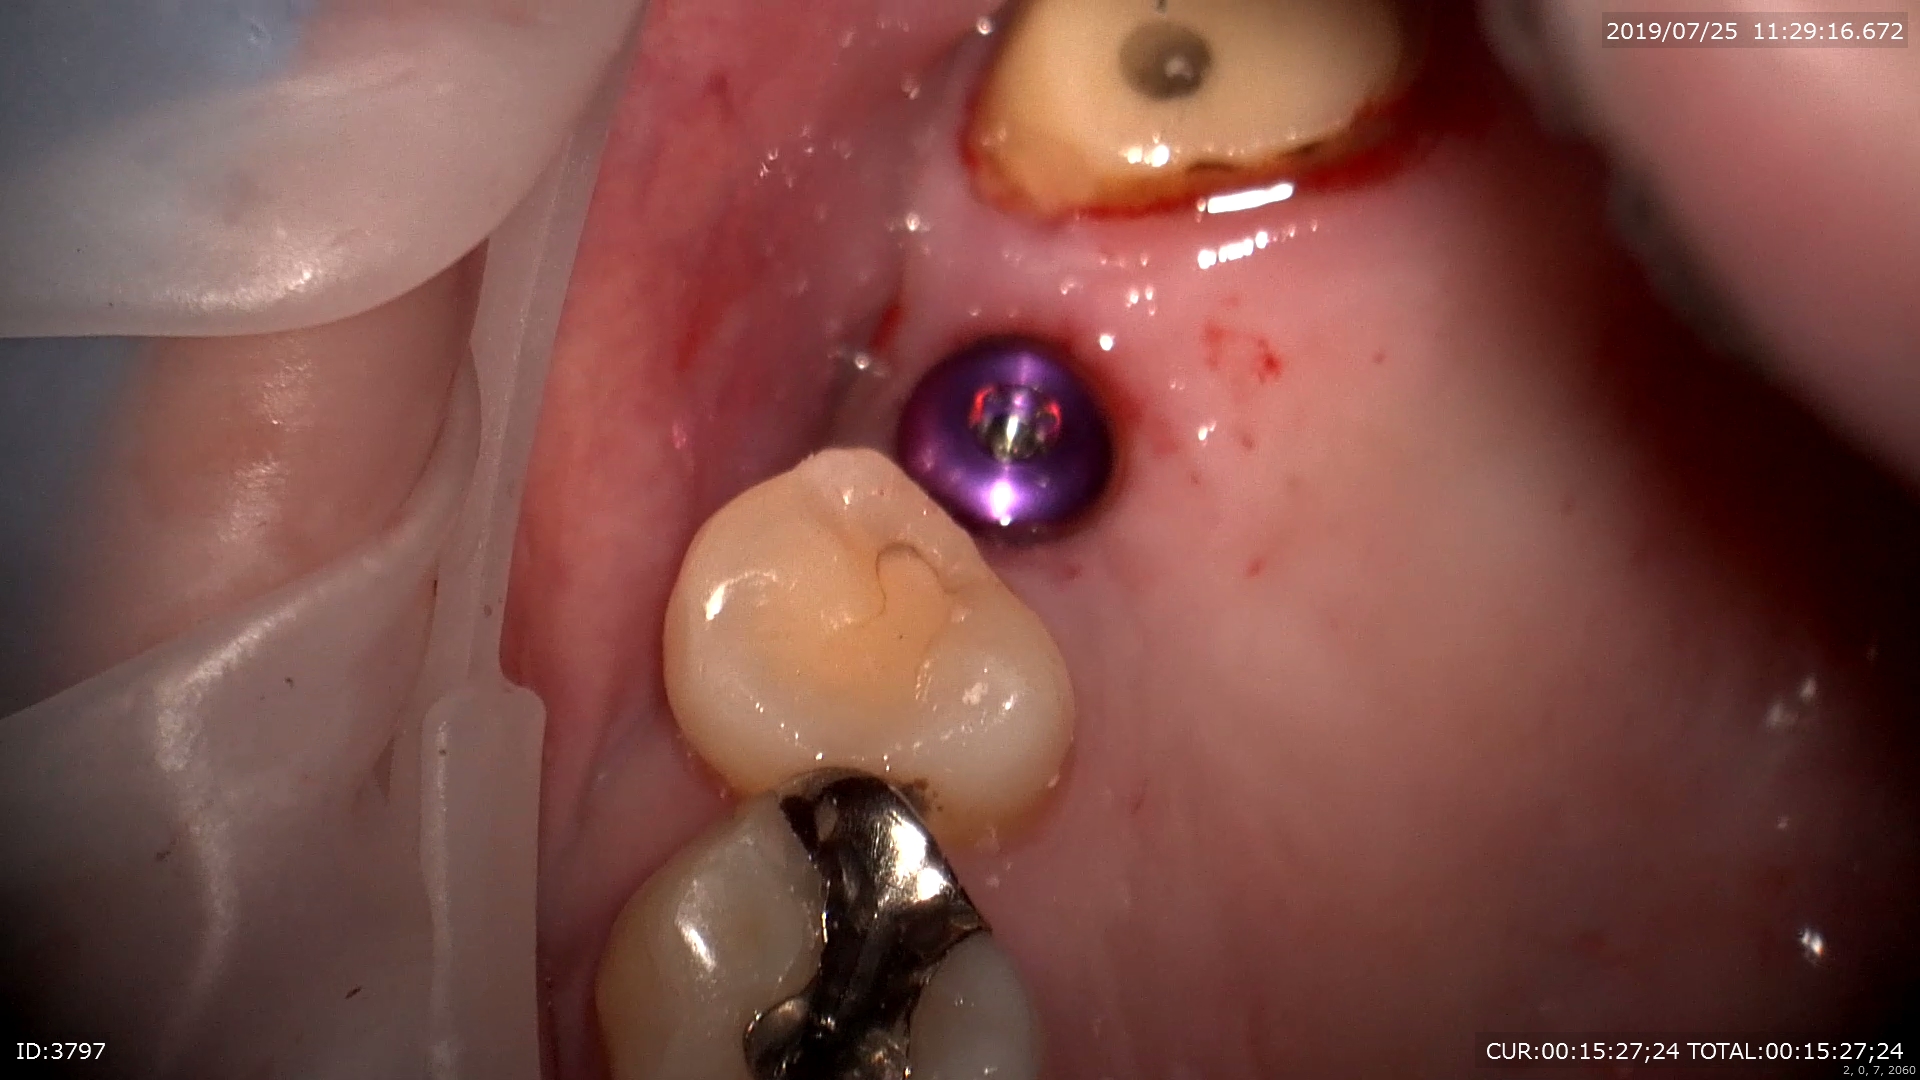

今日午前中のソケットリフトを併用したOPEも

ガイドを使用し

ハッチを開け

フルガイドで埋入

ほらメスも糸も使わない1回法。次回は型取り

右上の時間を見て頂ければ分かりますが

13分で終わっています。